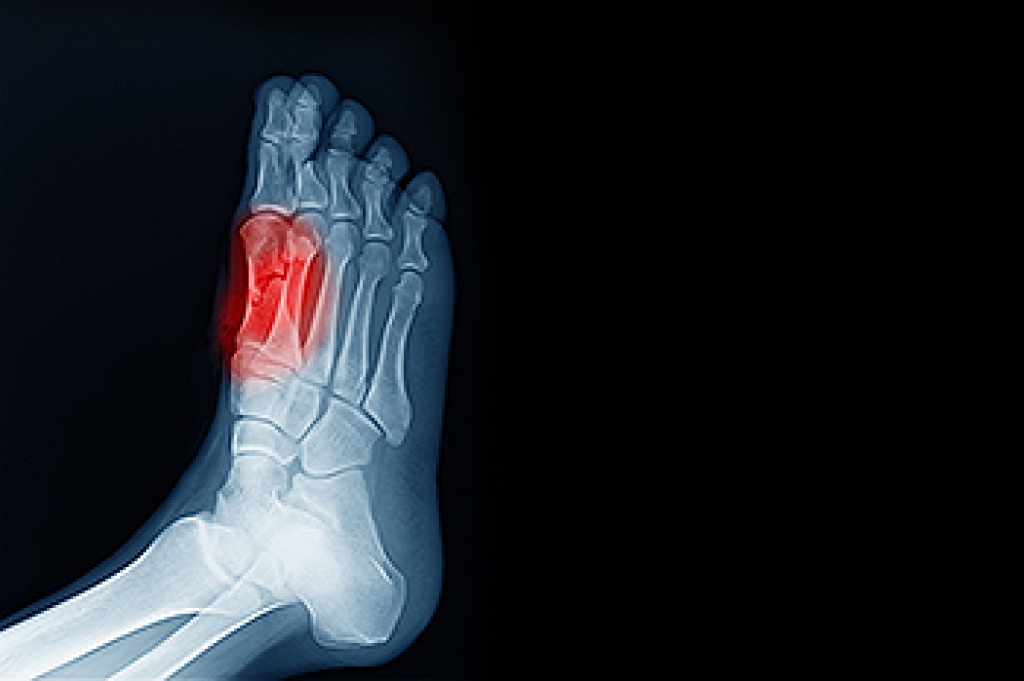

Diagnosis

To figure out the cause of foot pain, podiatrists utilize several different methods. This can range from simple visual inspections and sensation tests to X-rays and MRI scans. Prior medical history, family medical history, and any recent physical traumatic events will all be taken into consideration for a proper diagnosis.